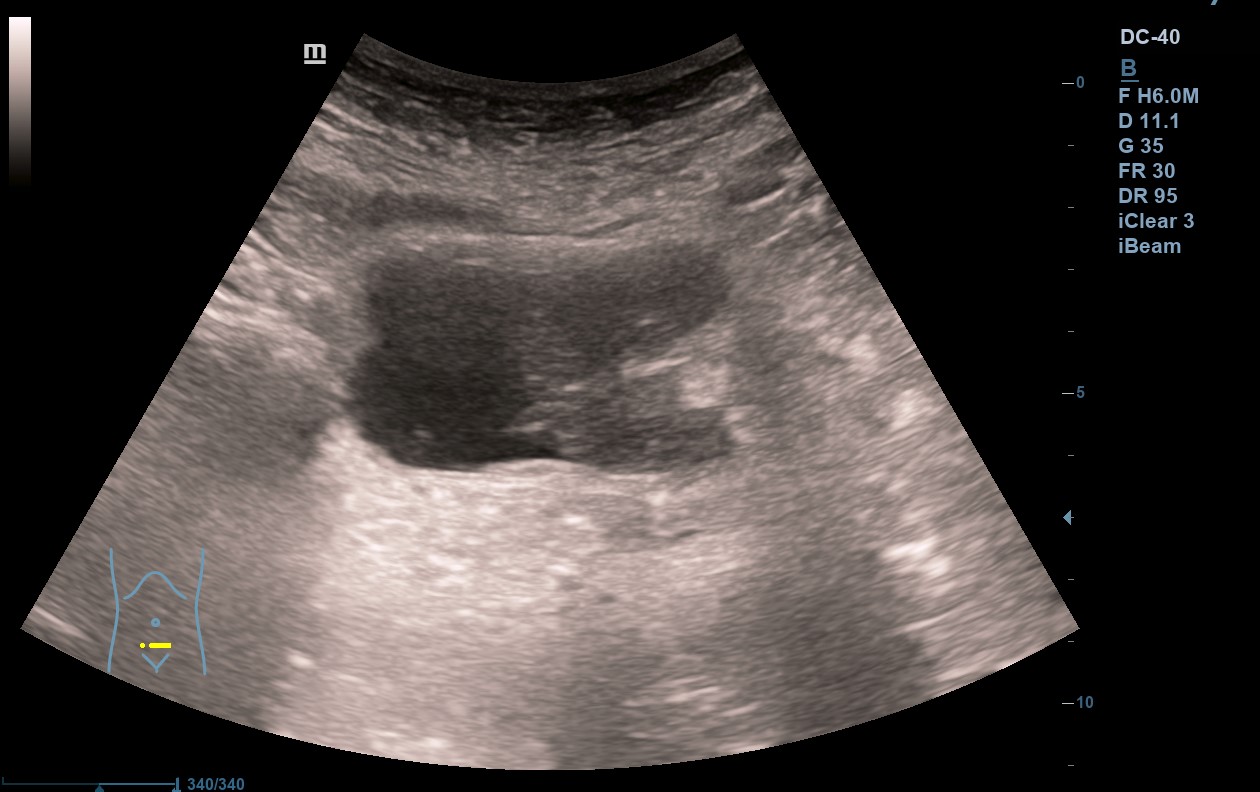

Hallazgos ecográficos

En analítica de control por Cardiología se evidencia anemia microcítica hipocrómica. En el estudio de la misma y concomitando con una infección de orina, se objetiva microhematuria, si bien no reseñable. Se trata la infección de orina y dada la desaparición de la sintomatología y la buena respuesta a tratamiento con ferroterapia, se cesa el estudio. Repite en dos ocasiones más ITU + microhematuria. Dada la continuidad de los episodios, realizamos ecografía en AP objetivando la presencia de una LOE intravesical, que se estudia en el ámbito hospitalario confirmado el diagnóstico de ca. uroterial.

Ecografía en AP: sospecha de tumoración intravesical. TAC abdómino pélvico: masa vesical dependiente de pared izquierda con hipercaptación, impresiona de diseminación a distancia. Uro-TC confirma ca. de vejiga. AP con carcinoma uroterial papilar de alto grado G3pT1. Estudio de extensión por el momento negativo.